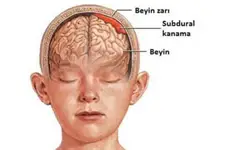

Beyinde kitle ameliyatı, genellikle tümörler, kist veya diğer anormal oluşumların cerrahi olarak çıkarılması amacıyla yapılan bir işlemdir. Bu tür bir ameliyat, beyin dokusuna doğrudan müdahale gerektiği için belirli riskler taşır ve sonrasında hastalar için çeşitli zorluklar ortaya çıkabilir. İşte bu makalede, beyin kitle ameliyatının riskleri ve sonrası hakkında detaylı bir inceleme yapılacaktır. 1. Beyin Kitle Ameliyatının Riskleri Beyin kitle ameliyatı, birçok risk barındırır. Bu riskler arasında şunlar bulunmaktadır:

4. Potansiyel Komplikasyonlar Ameliyat sonrası komplikasyonlar, hastanın genel sağlığını etkileyebilir. Bunlar arasında: